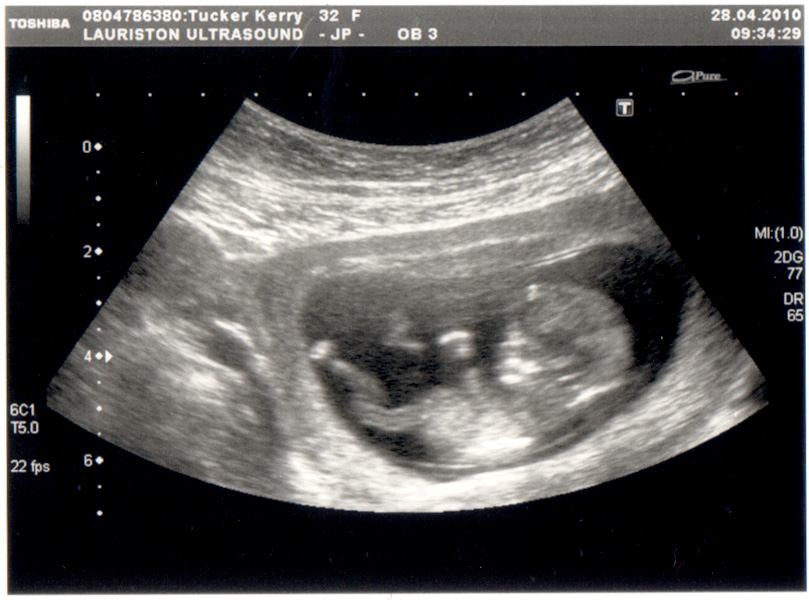

Exactly two years to the day since I last posted that we were expecting another baby, I'm proud to announce that we are… expecting another baby!

Baby Tucker-Turnbull number three is due on number two's birthday, November 10th.